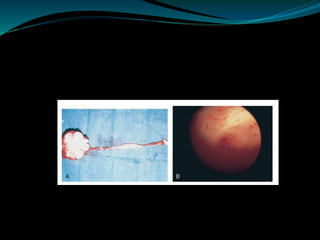

Cystoscopy and Ureteroscopy

 Endoscopy plays a limited role in the diagnosis of TB.

Despite direct visualization of lesions, there are no

pathognomonic findings that are specific for

tuberculosis.

 Ulcerative lesions may mimic malignancy. A “golf-

hole” ureteric orifice is suggestive of tuberculosis, and,

when found, upper tract imaging or endoscopy should

be obtained .

 However, a biopsy should be done when in doubt of

malignancy.